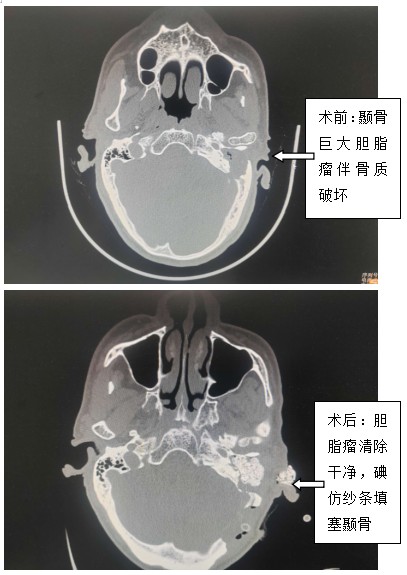

近年來,姚大爺被檢查出來有糖尿病,所以每次去醫(yī)院總是為了控制血糖。一星期前,姚大爺再次出現(xiàn)耳部流膿及血糖控制不佳,往醫(yī)院抽血檢查竟然發(fā)現(xiàn)血糖20.3mmol/l。醫(yī)生建議住院治療,可是姚大爺在住院后經(jīng)過控制血糖后,發(fā)現(xiàn)耳朵雖然不流膿了,但是頭痛的越來越厲害,而且出現(xiàn)走路不穩(wěn)癥狀,一查CT,竟然發(fā)現(xiàn)小腦出現(xiàn)了一個30*20mm的膿腫,同時左側(cè)中耳及顳骨有一個巨大腫瘤(膽脂瘤),于是當(dāng)?shù)蒯t(yī)院通過醫(yī)聯(lián)體??坡?lián)盟專家會診,建議轉(zhuǎn)院急診手術(shù)。經(jīng)過長達5小時的手術(shù),術(shù)中耳鼻喉科茹江云、庾江東、漆德良團隊顯微鏡下清除中耳及顳骨巨大膽脂瘤,同時神經(jīng)外科李遠志、李芳團隊予以行乙狀竇后入路小腦膿腫清除手術(shù),病人暫時脫離生命危險。